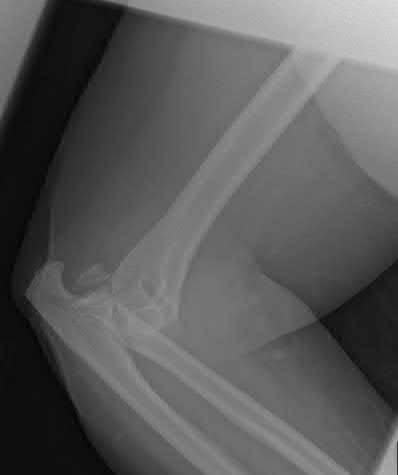

In Lichtman Stage IIIA Kienböck's disease, there is lunate collapse but carpal height and alignment (scaphoid) are maintained. For a patient with Stage IIIA disease and ulnar negative variance, a joint-leveling procedure such as a radial shortening osteotomy is the most appropriate and biomechanically sound intervention, as it decreases load transmission through the radiolunate fossa. Proximal row carpectomy or STT fusion are typically reserved for more advanced stages (IIIB or IV).

Question 72

An 85-year-old female with severe rheumatoid arthritis and osteoporosis sustains a highly comminuted, intra-articular distal humerus fracture (AO/OTA 13-C3) after a mechanical fall. She lives independently and uses a walker. Which surgical intervention provides the most predictable pain relief and allows for immediate postoperative weight-bearing through the upper extremity for mobility?

Explanation

In an elderly, osteoporotic patient (especially with a history of inflammatory arthritis like RA) who sustains a highly comminuted intra-articular distal humerus fracture, Total Elbow Arthroplasty (TEA) provides superior outcomes compared to ORIF. It offers more predictable pain relief, earlier return of function, and allows the patient to bear weight immediately (within standard TEA limits, though essential for immediate walker use) without the high risk of hardware failure or nonunion associated with osteoporotic bone.